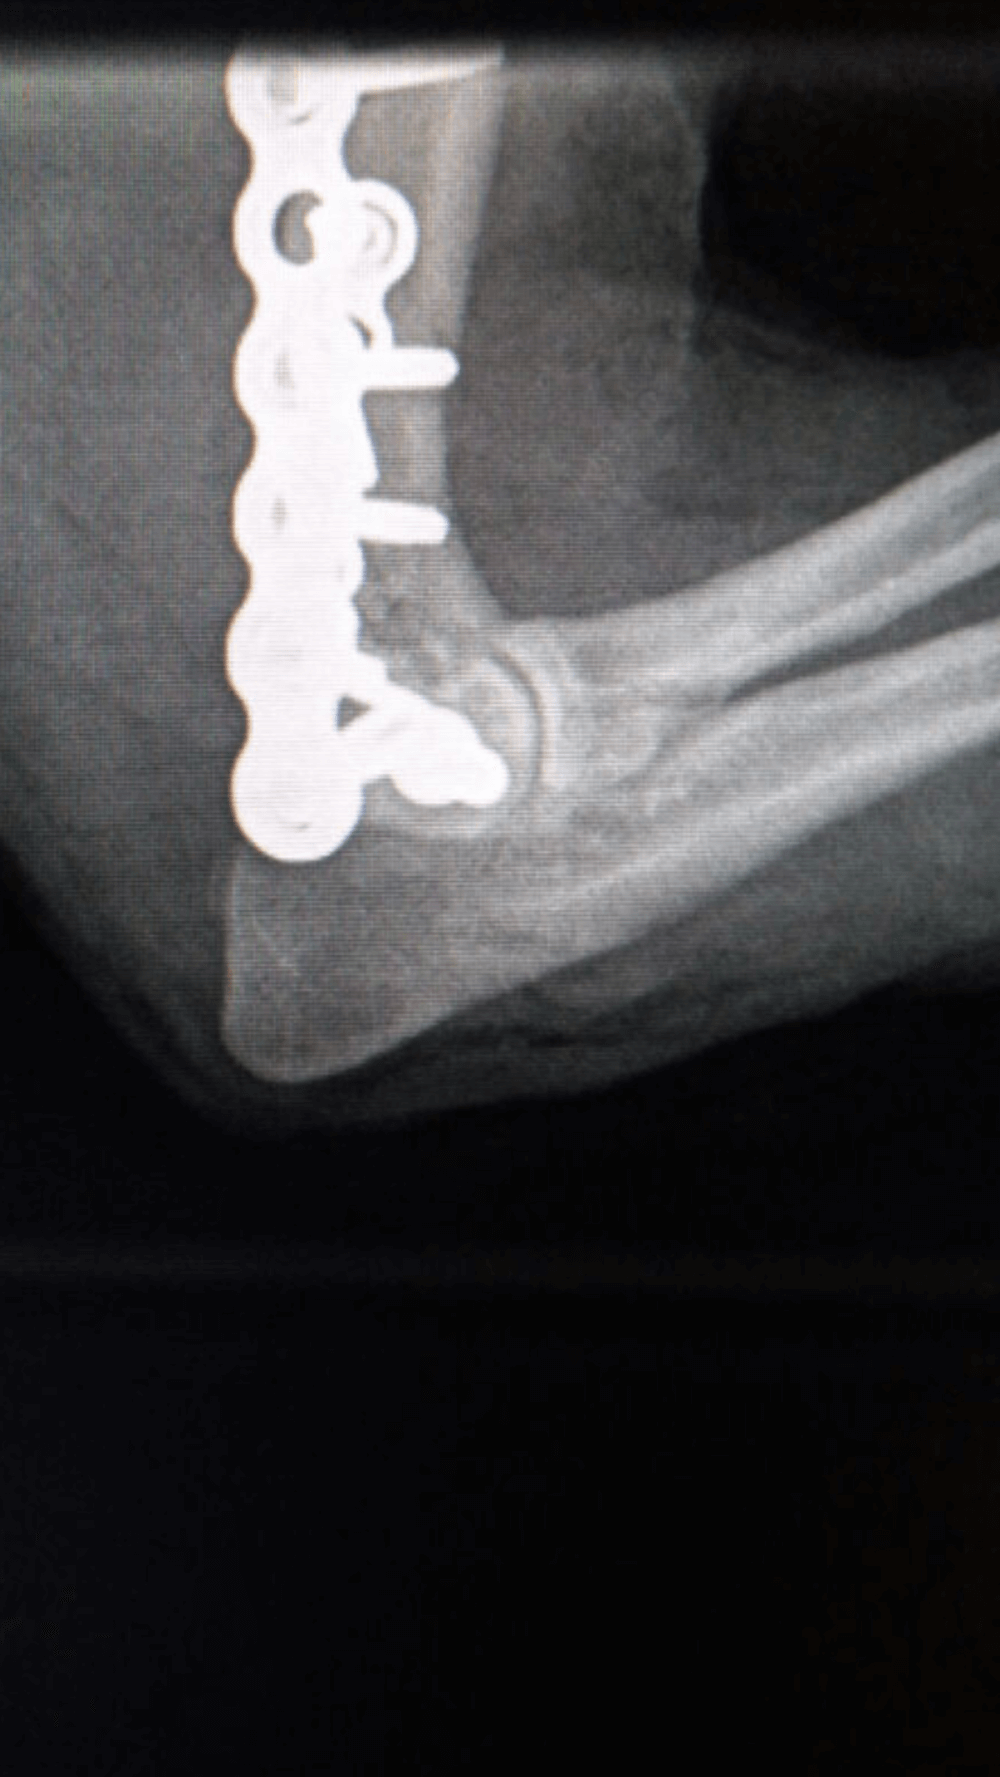

Radius and Ulna Fracture Repair

Example of Minimally Invasive Radius and Ulna Fracture Repair.